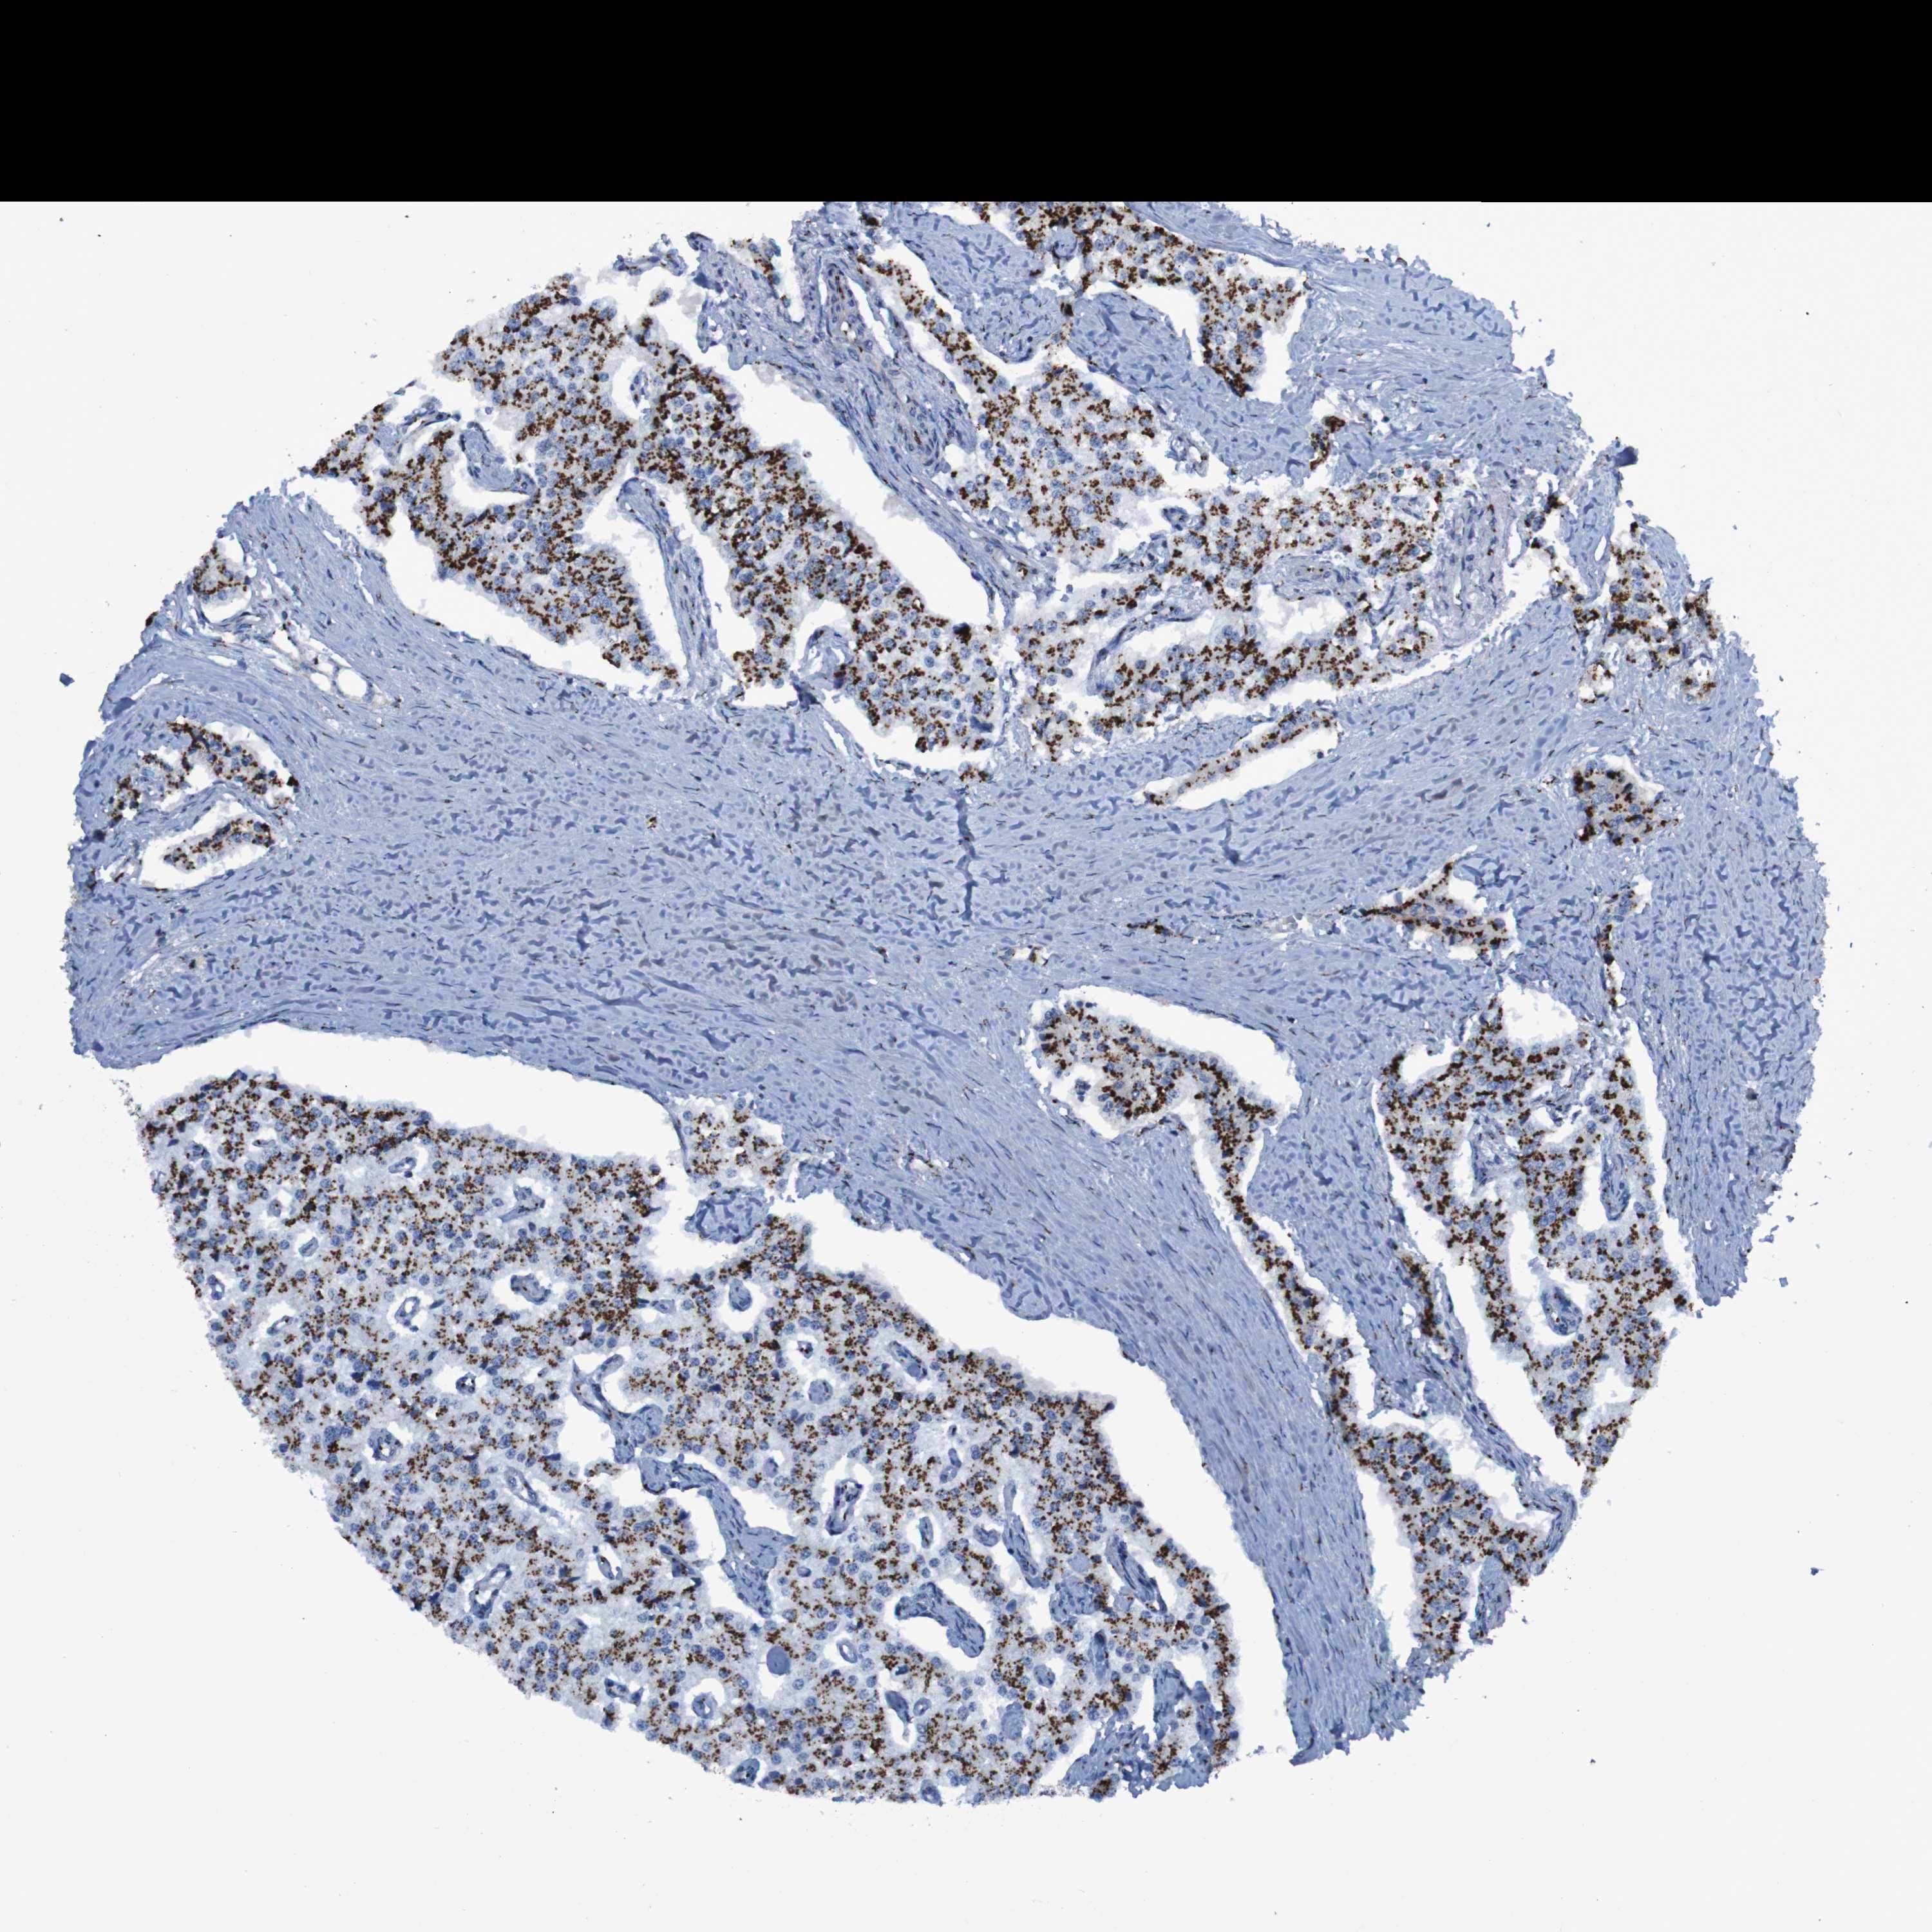

CARCINOID - Protein expressioni

A mouse-over function shows sample information and annotation data. Click on an image to view it in a full screen mode. Samples can be filtered based on level of antibody staining by selecting one or several of the following categories: high, medium, low and not detected. The assay and annotation is described here.

Antibody stainingi

Antibody staining in the annotated cell types in the current human tissue is reported as not detected, low, medium, or high, based on conventional immunohistochemistry profiling in selected tissues. This score is based on the combination of the staining intensity and fraction of stained cells.

Each image is clickable and will lead to virtual microscopy that enables deeper exploration of all samples and also displays staining intensity scores, fraction scores and subcellular localization as well as patient and tissue information for each sample.

Antibody CAB015341

Staining

Medium

Moderate

75%-25%

Nuclear

Carcinoid, malignant, NOS